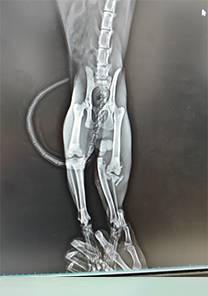

Veysel Bey'in Kedisi Paşa

Veysel Bey'in kedisi Paşa'nın tibiave fibulasının proksimalinde distal kırık tespit edilmiştir. Operasyon günü itibarıyla MN - HUND&KATT kullanılmıştır. Operasyondan sadece 14 gün sonra eksternal fiksatör takılan kediden pinler çıkarılmış ve tamamen iyileşmiştir.